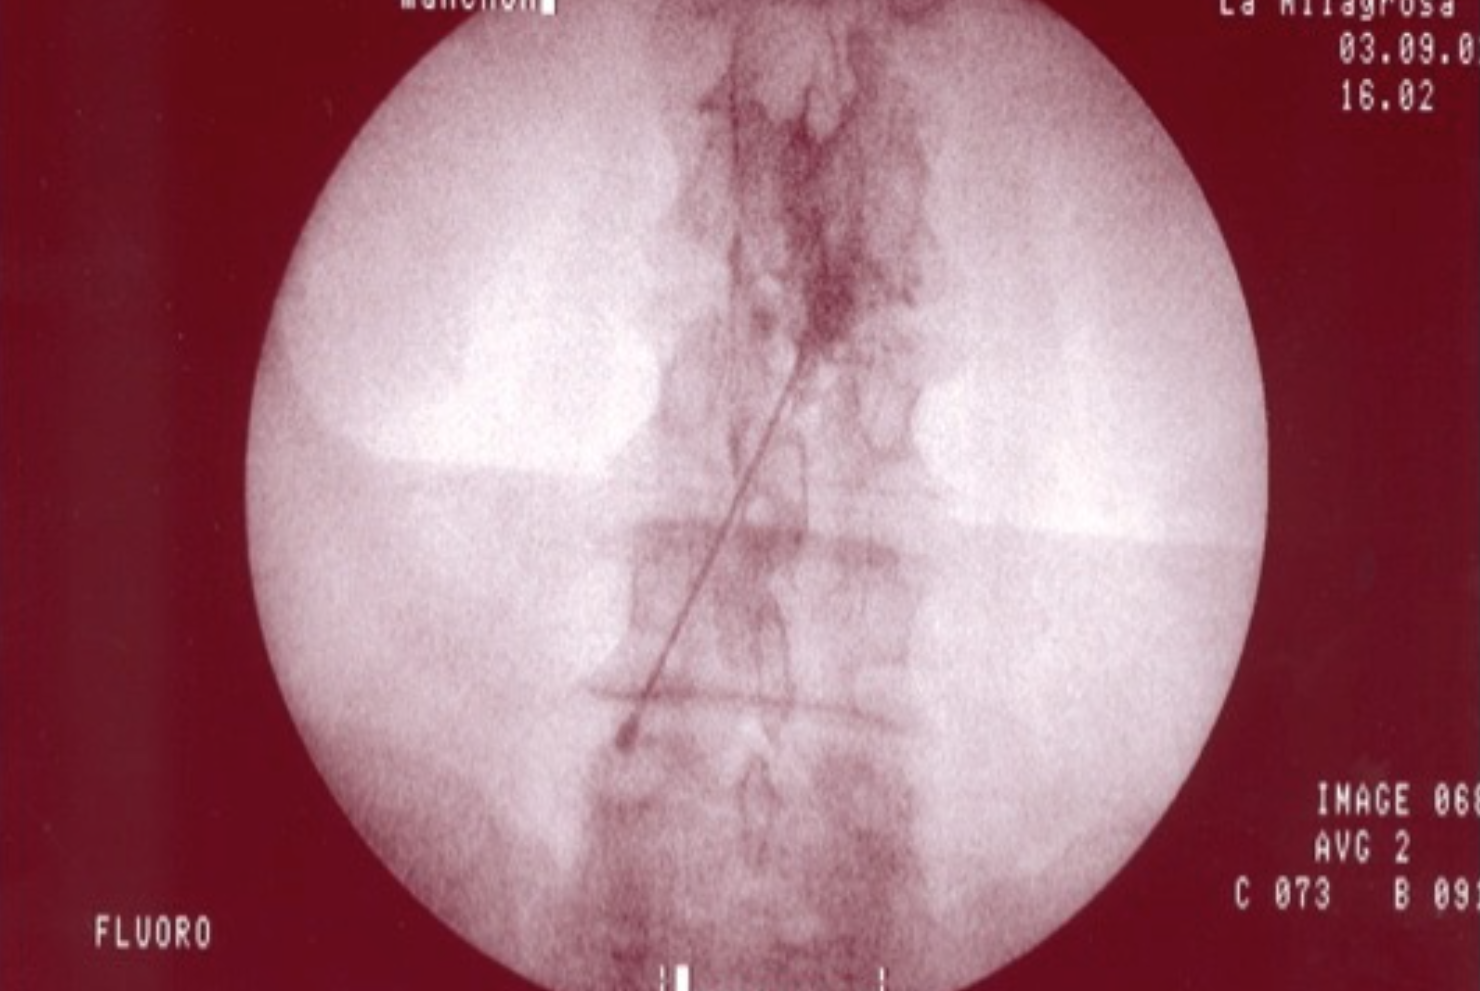

TÉCNICA

Con el paciente en decúbito prono, con almohada en el abdomen para corregir la lordosis fisiológica, se coloca el arco de fluoroscopia en en posición AP para localizar el espacio a tratar y se moviliza craneocaudalmente para eliminar el doble contorno. Una vez corregido el doble contorno se coloca el arco de rayos en posición oblicua ipsilateral (20-30º) hacia el lado afecto hasta localizar la imagen del  “perrito escocés”, y con un marcador radiopaco se localiza el target, que se encuentra en la unión de la cabeza con el cuello del perrito (6 horas de la aguja del reloj), se pinta con antiséptico la zona y se infiltra con anestésico local la dermis, tejido celular subcutáneo y planos musculares, insertándose la aguja (espinal 22G) en visión túnel. Se recoloca el arco de fluoroscopia en en posición lateral y se va avanzando la aguja hasta el extremo interno del foramen, momento en el que se administra contraste radiopaco a tiempo real, debiendo difundir al espacio epidural anterior. Se comprueba con el arco de fluoroscopia en en posición AP la difusión del contraste y se procede a la administración de la medicación (anestésico local y corticoide) que se realiza con mínima resistencia, y se finaliza con la retirada de la aguja con el mandril y la colocación de un apósito estéril.